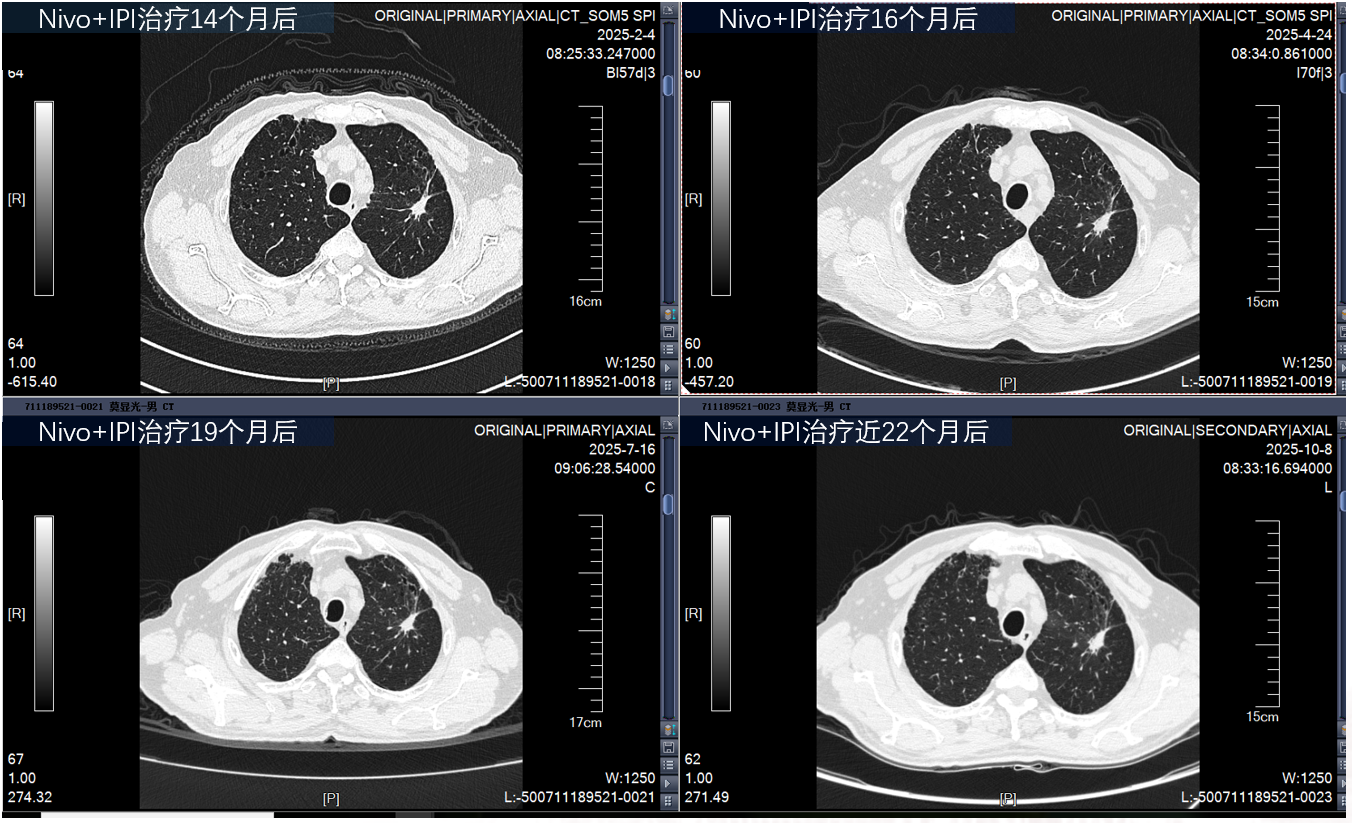

影像学复查(持续PR),PFS超过24个月

5.png

刘克军教授:本病例为一位 75 岁的高龄患者,确诊为 IVB 期左肺腺癌,伴双侧肾上腺转移。分子病理提示 EGFR/ALK 阴性,KRAS G12C 突变,PD-L1 阳性。鉴于患者高龄、家属对化疗耐受性的担忧以及对生活质量的诉求,经过慎重评估,选择 “纳武利尤单抗+伊匹木单抗”的双免一线治疗方案。结果显示,患者在治疗 3 个月后即达到部分缓解(PR),病灶缩小幅度超过 60%。截至目前,患者PFS超过24个月,且仍处于持续缓解状态,生活质量优异,实现了晚期肺癌的“慢病化”管理。这一成功案例不仅是精准医疗的体现,也为临床处理高龄复杂病例提供了宝贵的参考。

本例患者 PD-L1 阳性,属于免疫治疗的优势人群。CheckMate 227 研究 6 年随访数据显示,对于 PD-L1≥1% 的人群,双免组的中位 OS 达到 17.1 个月,6 年 OS 率达 22%。此外,研究显示肿瘤退缩程度与长期生存密切相关。若患者肿瘤退缩达到 50%-80%,其 6 年生存率可高达 50%。本例患者病灶缩小达 63.6%,正符合这一深度缓解特征,预示着极佳的长期生存前景。双免治疗起效后往往能带来超长期的缓解(DOR),CheckMate 227 中位 DOR 长达 24.5 个月,远超化疗组。

CheckMate 227 研究及长期临床实践表明,通过合理的剂量安排(纳武利尤单抗 3mg/kg q2w + 伊匹木单抗 1mg/kg q6w),大多数免疫相关不良反应(irAEs)是可逆且可管理的。在本例患者中,除了生存期的延长,最令人欣慰的是患者优异的生活质量。PFS超过24个月的治疗过程中,患者未发生严重不良反应,充分证明了该方案在高龄人群中的耐受性。且采用“纳武利尤单抗 q2w + 伊匹木单抗 q6w”的给药模式,无需住院,门诊输注即可,极大地提高了患者的便利性和依从性。